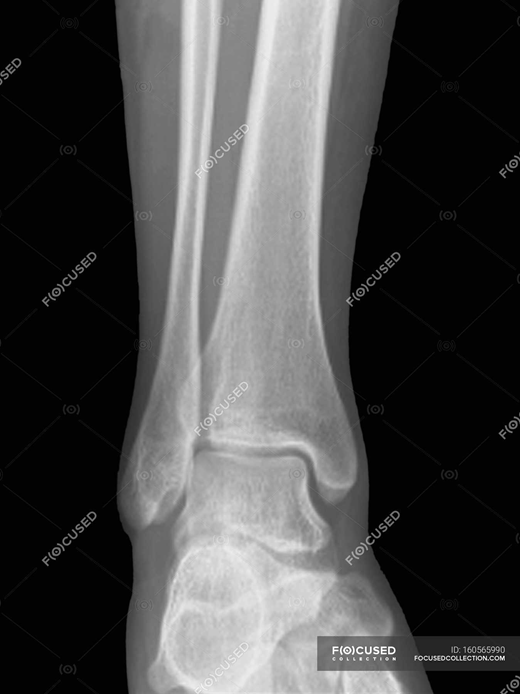

Запитання 16

РОЗПІЗНАЙТЕ КІСТКУ ТА ЇЇ ЧАСТИНУ, ЯКУ ВИ ЛЕГКО МОЖЕТЕ ПРОПАЛЬПУВАТИ У СЕБЕ.

варіанти відповідей

FIBULA

TIBIA

ПЕРЕДНІЙ ГОСТРИЙ КРАЙ

12

13

ГОРБИСТІСТЬ

МЕДІАЛЬНА КІСТОЧКА

ГОЛОВКА

ДЕ ВИ БАЧИТЕ КІСТКУ, ЩО РОЗТАШОВАНА З ЛАТЕРАЛЬНОЇ СТОРОНИ ГОМІЛКИ?

Запитання 56

СУГЛОБ УТВОРЕНИЙ СУГЛОБОВИМИ ПОВЕРХНЯМИ ЛАТЕРАЛЬНОЇ І МЕДІАЛЬНОЇ КІСТОЧКИ ТА ТІЛОМ ТАРАННОЇ КІСТКИ. РУХИ НАВКОЛО ФРОНТАЛЬНОЇ ОСІ. ЧАСТО - РОЗТЯЖІННЯ, ВИВИХИ, РОЗРИВИ, ПЕРЕЛОМИ. РОЗПІЗНАЙТЕ СУГЛОБ.

КОЛІННИЙ С.

ГОМІЛКОВО-СТОПНИЙ С.

КУЛЬШОВИЙ С.

ЛІКТЬОВИЙ С.

ПЛЕЧОВИЙ С.

ПРОМЕНЕВО-ЗАП'ЯСТКОВИЙ С.